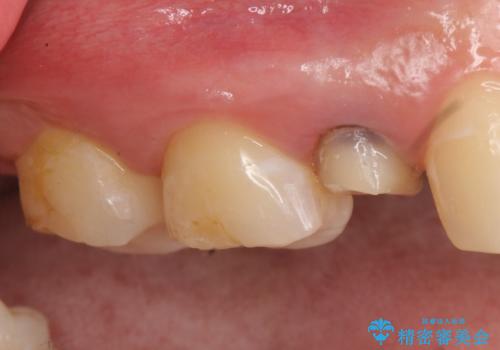

- 他院にて右上5番目の歯の根管治療を行っていたが、痛みが引かないため当院にいらっしゃった方の症例です。

右上5は再根管治療を行い症状の緩解を確認後、オールセラミッククラウンによる補綴を行いました。

右上6、7番目の歯もしみるとのことだったので古い樹脂及び虫歯を除去後、オールセラミッククラウンによる補綴を行いました。

※右上5は歯肉縁下まで虫歯だったため歯冠長延長術を提案しましたが、希望されませんでした。